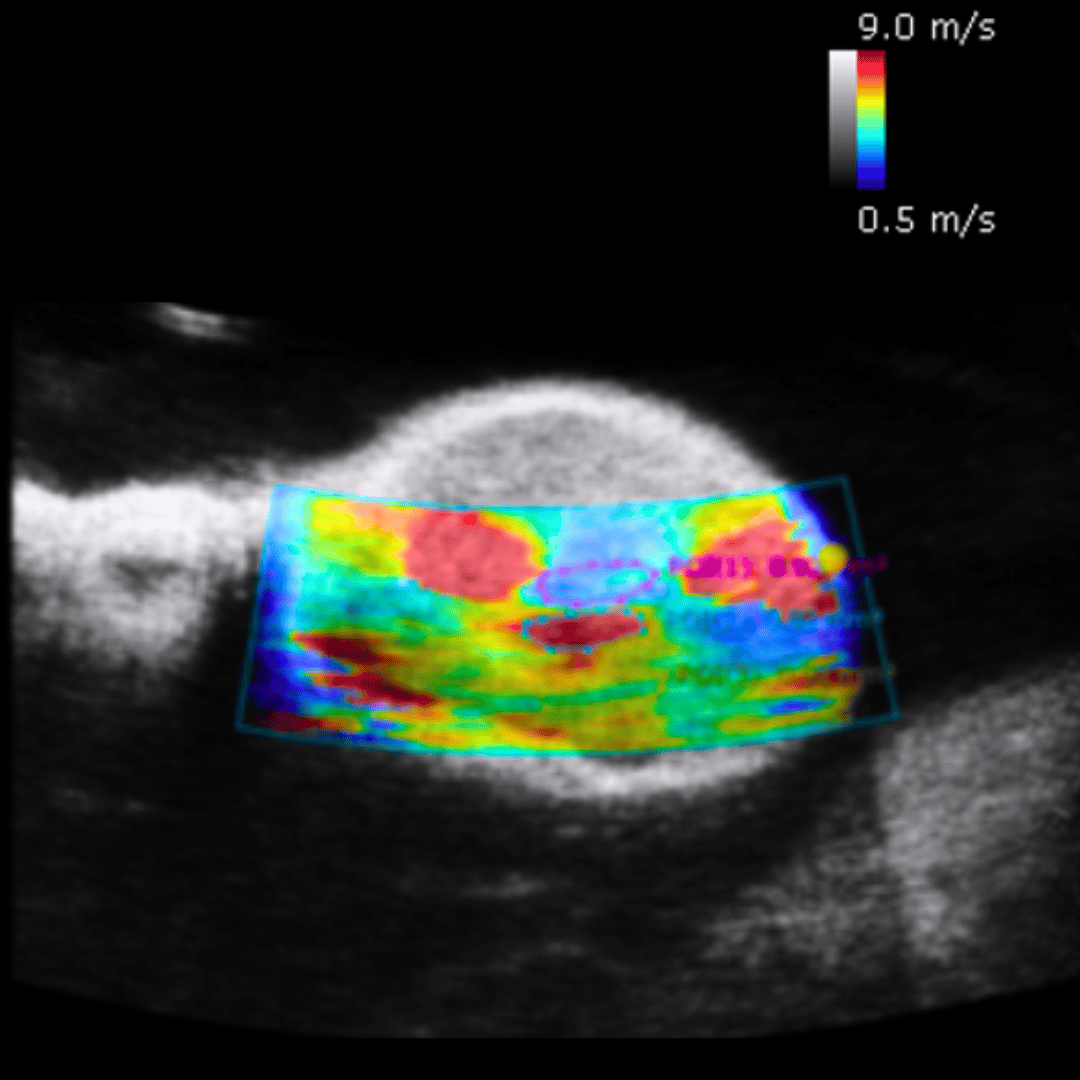

Shear wave Elastography PT2